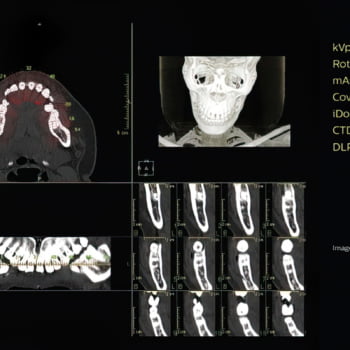

A exclusiva tecnologia MAR reduz os efeitos de objetos metálicos na formação das imagens, permitindo a visualização da anatomia circundante. Nossa alta resolução espacial revela detalhes sutis para um alto nível de análise quantitativa, maximizando a detectabilidade de pequenos objetos.